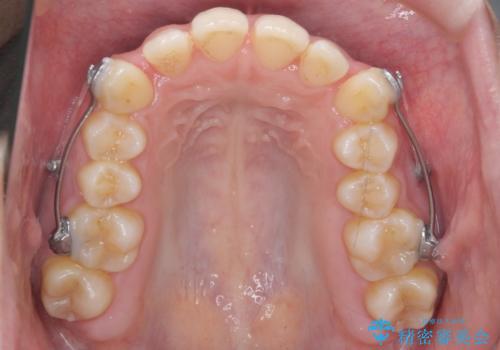

- 矯正装置

- ワイヤー矯正

後ろに下げるために、ワイヤー矯正の前にカリエールという装置を使用しました。